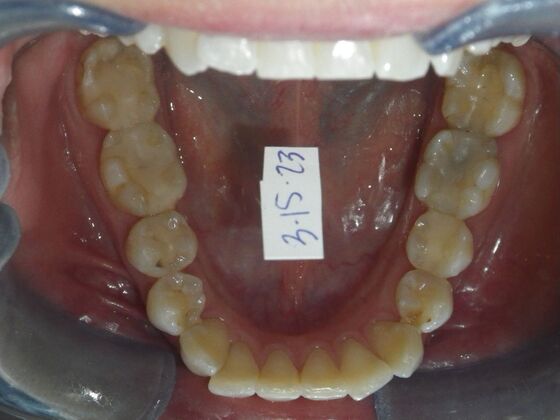

This patient had concerns with the lower anterior teeth. There were some slight rotations and the midline of the lower incisors wasn't lined up with the upper midline. To correct this we used slenderizing of teeth in strategic areas of the lower arch to correct the rotations and line up the midlines. Patient very pleased with the results.